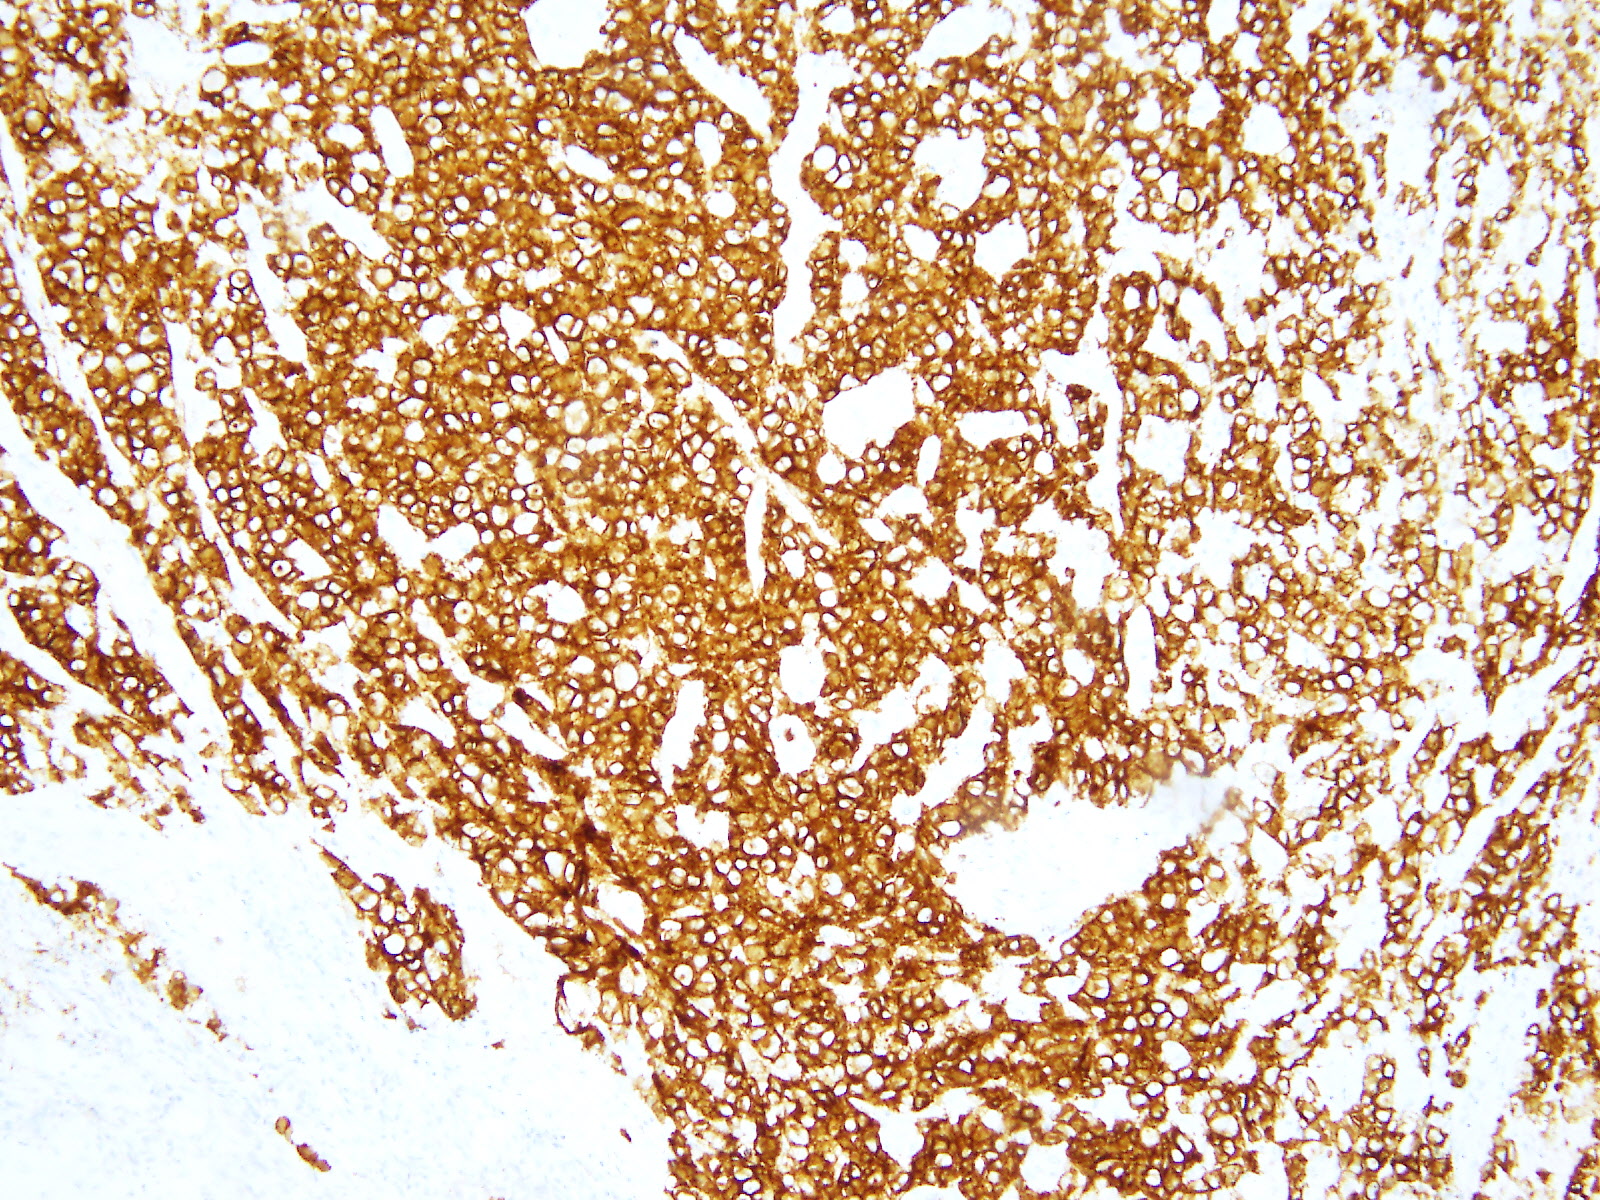

同時に提出された胃生検の免疫染色で、上皮性のマーカーやCD3、CD20は(−)、ALK-1(+)、CD30(+)で、ALK陽性未分化大細胞型リンパ腫と診断された。

HE×10 HE×20 ALK-1×10 CD30×10